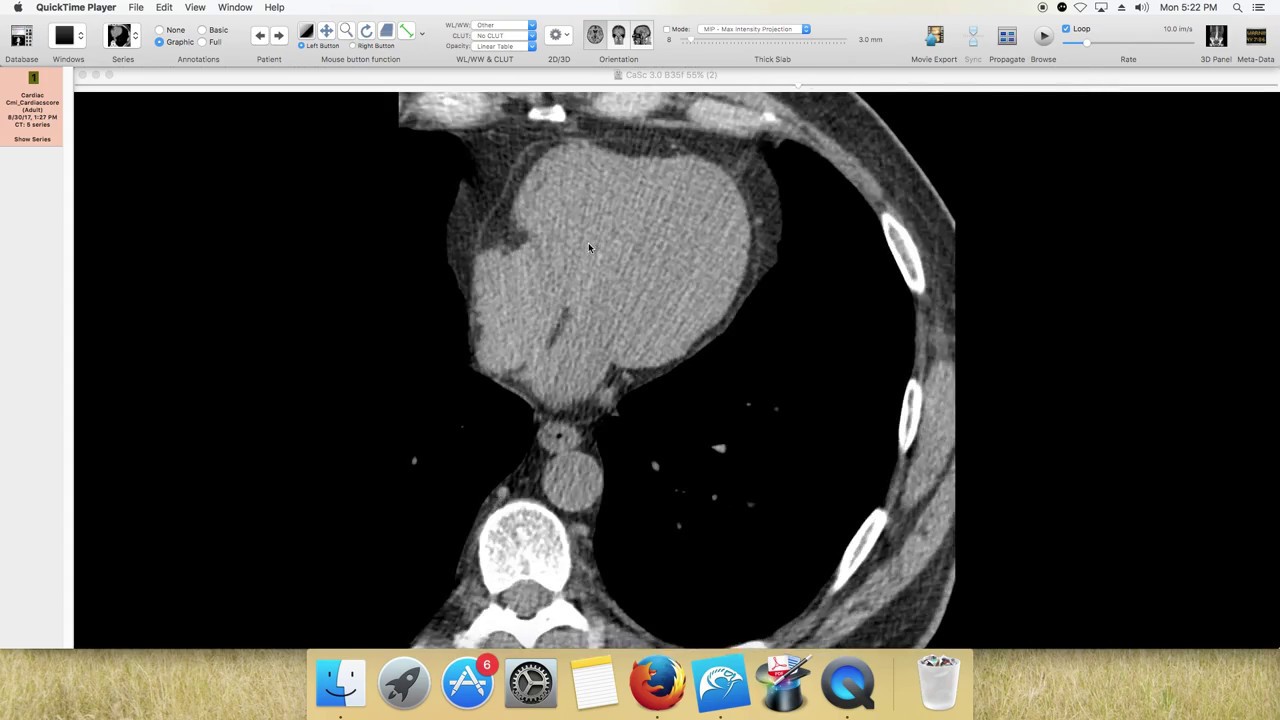

Coronary Artery Calcium Score Bluegrass Regional Imaging There are currently three cac scoring methods: agatston score, volume score, and mass score (table 1). of these three cac scoring methods, the agatston method is the most validated and widely used in practice, thereby serving as the reference standard. In this review, we report on the lessons learned from the largest retrospective clinical cohort of cac scoring yet assembled, with direct relevance to practicing radiologists and cardiologists using cardiac ct for risk stratification. data on cac in young adults are generally limited. The purpose of this ct scan is to determine a coronary artery calcium score. this score is determined by the number, size and density (thickness) of the calcifi ed plaque in the coronary arteries that supply blood to your heart. This jama insights explores how coronary artery calcium and computed tomography calcium scores can improve risk assessment for atherosclerotic.

Coronary Artery Calcium Scoring Current Status And Future Directions The purpose of this ct scan is to determine a coronary artery calcium score. this score is determined by the number, size and density (thickness) of the calcifi ed plaque in the coronary arteries that supply blood to your heart. This jama insights explores how coronary artery calcium and computed tomography calcium scores can improve risk assessment for atherosclerotic. Understanding the importance of the coronary artery calcium (cac) score and its interpretation is advantageous to the physician and the patient. this review will provide an explanation of the recent advances in cac scoring, which the caregiver can utilize to determine the best approach for treatment recommendations. The indications for and approach to obtaining a cac score, along with the diagnostic and prognostic implications of cac scoring, will be reviewed here. the use of multidetector ct and other modalities for noninvasive coronary angiography are discussed separately. A ct coronary calcium score is a simple, non invasive test that measures the amount of calcified plaque in your heart’s arteries. this specialized ct scan can help determine your risk of heart disease and heart attack. Ct based abdominal aortic calcification is a strong predictor of future cardiovascular events, outperforming the framingham risk score. this finding suggests a potential opportunistic role in abdominal nonenhanced ct scans performed for other clinical indications (7).